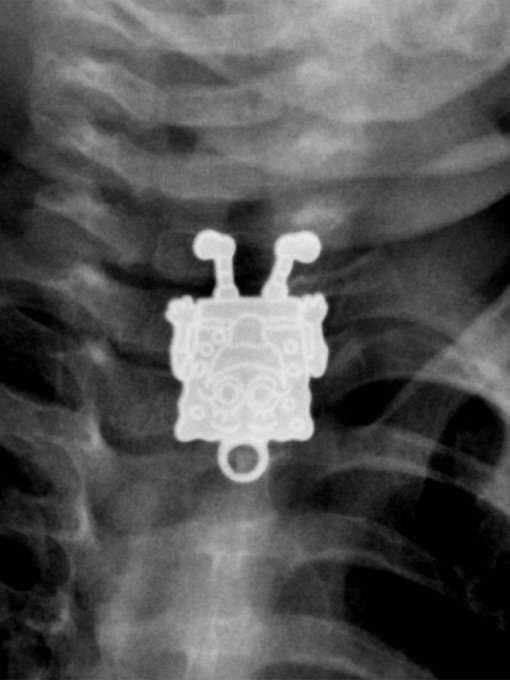

14. 疴…那是海绵宝宝吗?

一些奇怪的X光照片,看完整个人都不好了……-14.jpg